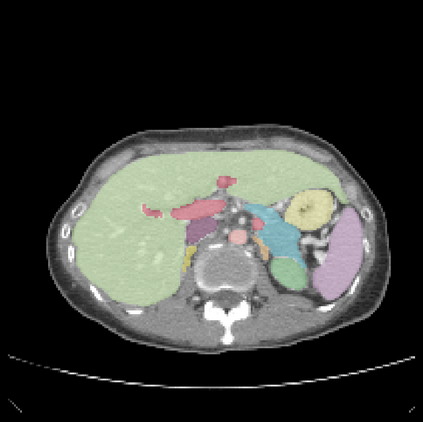

It is imperative to ensure the robustness of deep learning models in critical applications such as, healthcare. While recent advances in deep learning have improved the performance of volumetric medical image segmentation models, these models cannot be deployed for real-world applications immediately due to their vulnerability to adversarial attacks. We present a 3D frequency domain adversarial attack for volumetric medical image segmentation models and demonstrate its advantages over conventional input or voxel domain attacks. Using our proposed attack, we introduce a novel frequency domain adversarial training approach for optimizing a robust model against voxel and frequency domain attacks. Moreover, we propose frequency consistency loss to regulate our frequency domain adversarial training that achieves a better tradeoff between model's performance on clean and adversarial samples. Code is publicly available at https://github.com/asif-hanif/vafa.